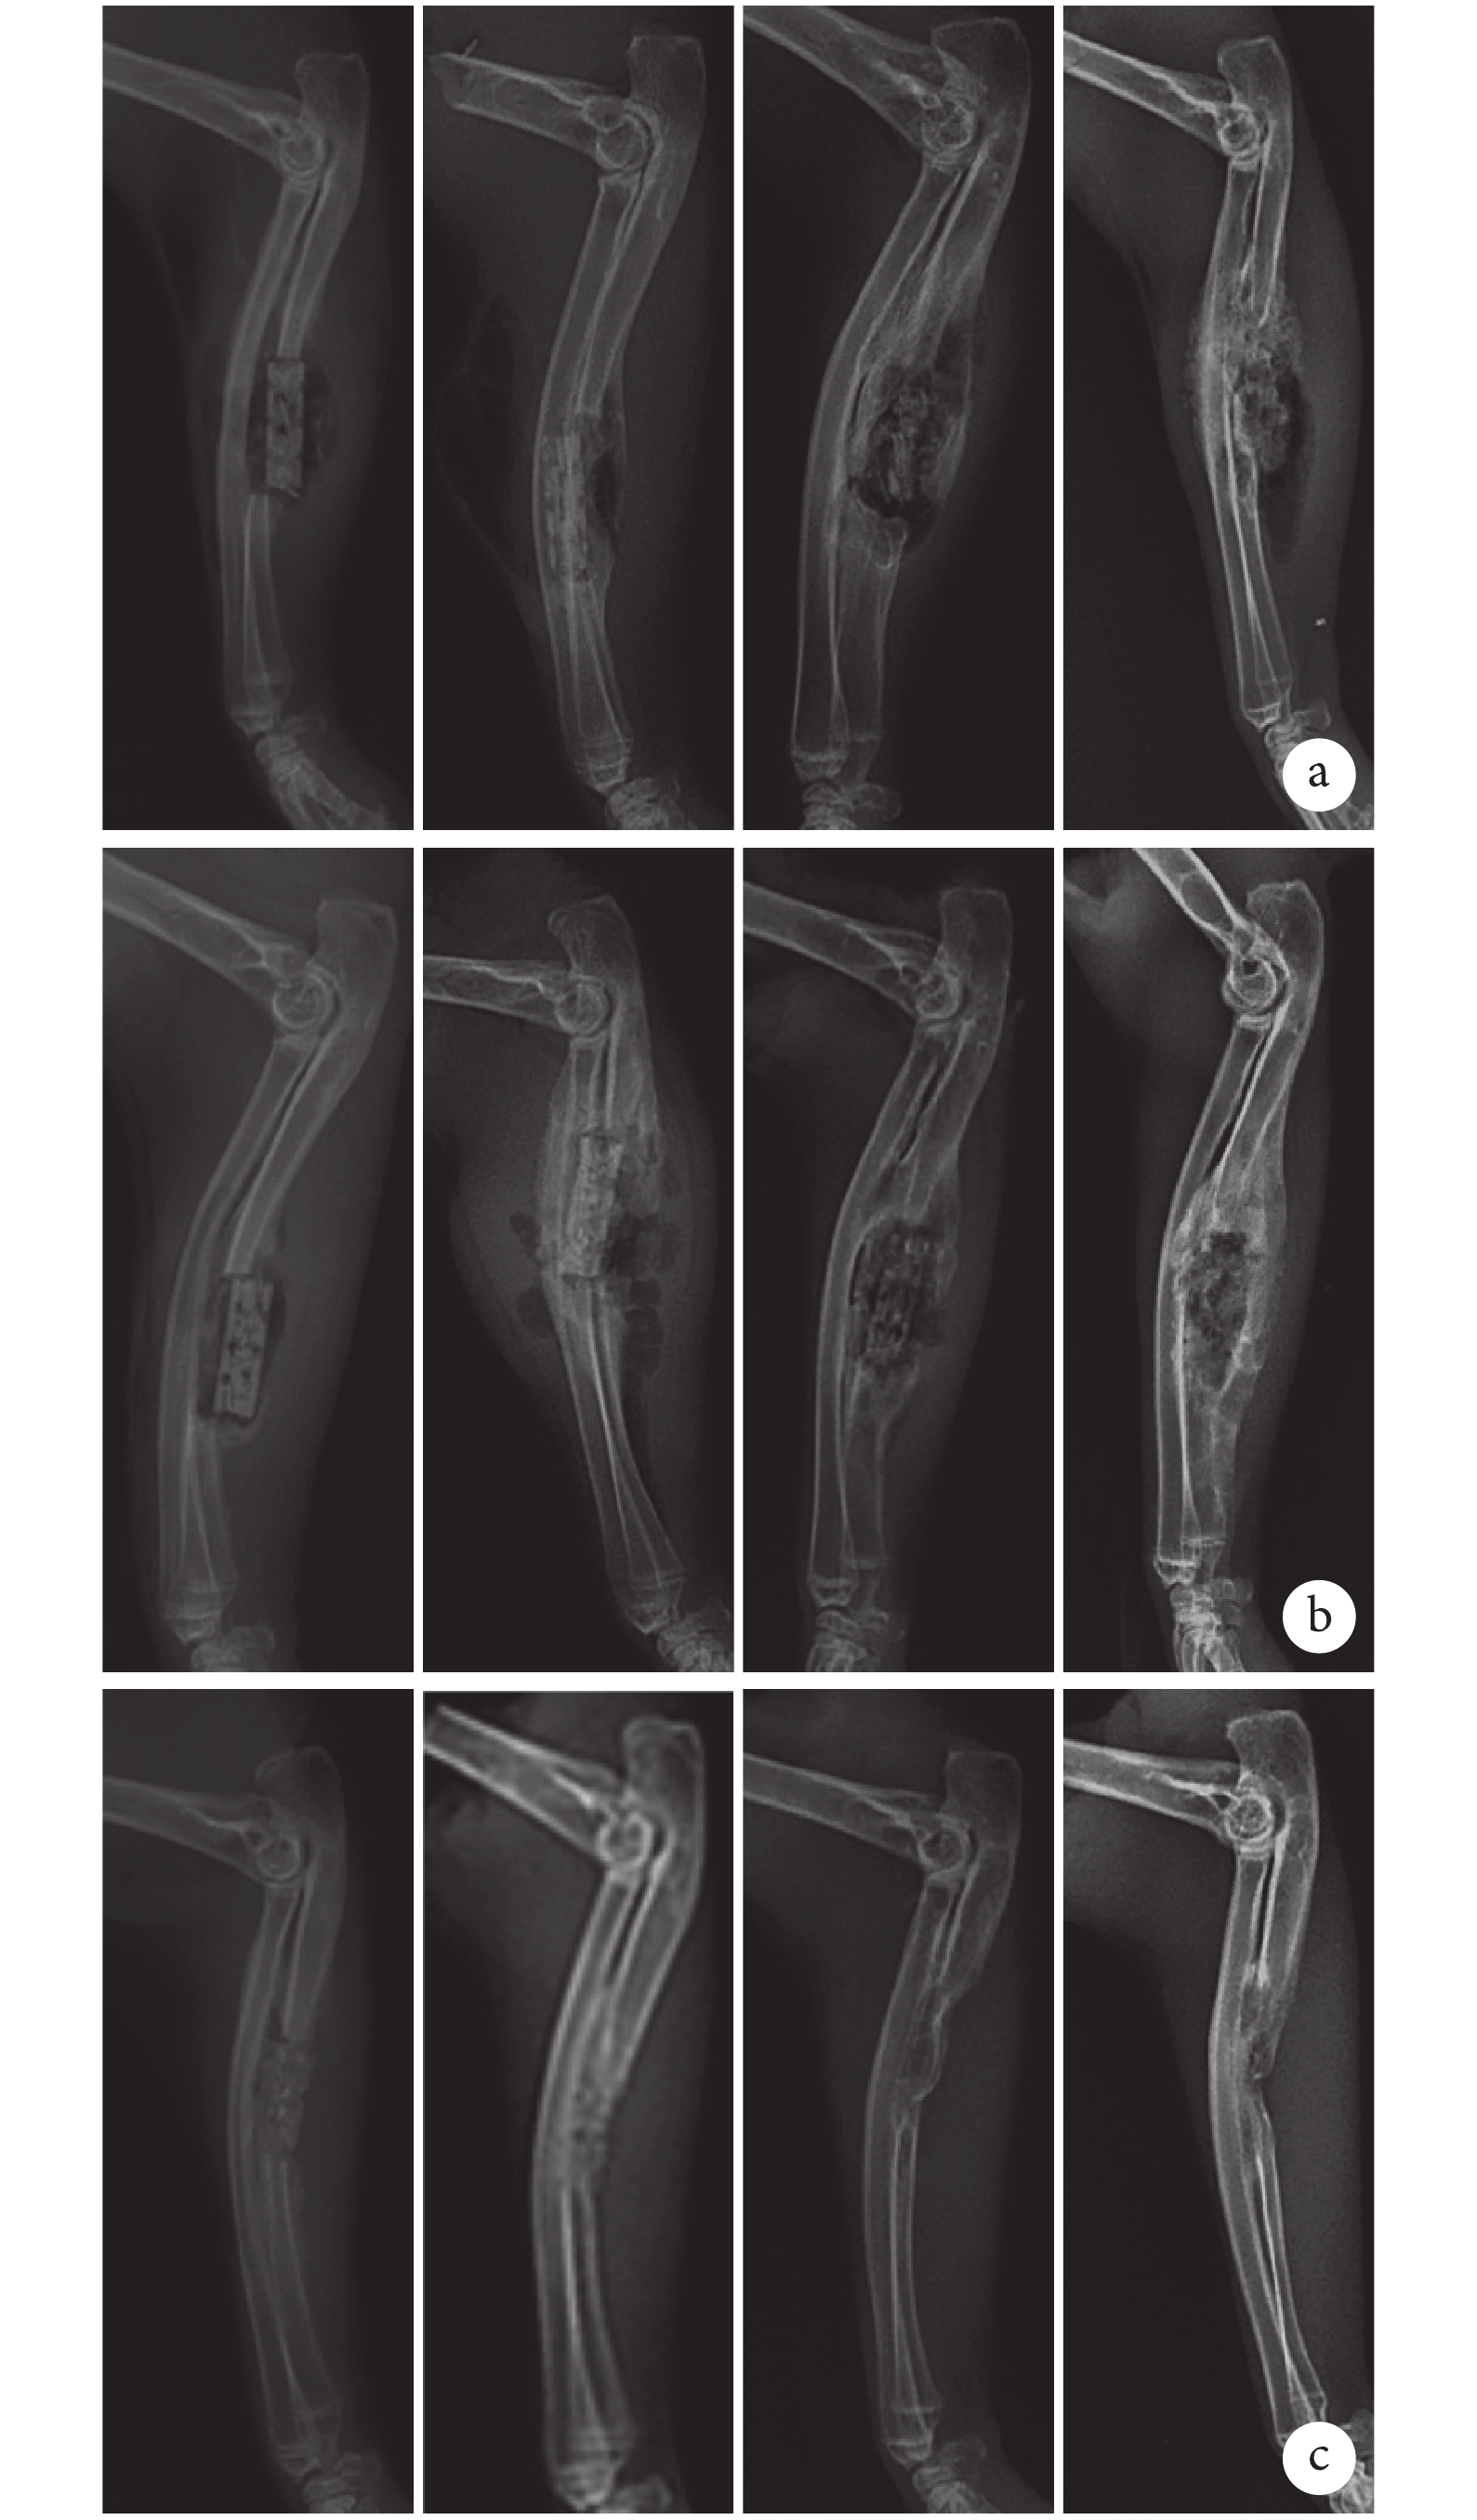

X 線片觀察示,術后 2 周時各組均未見明顯骨痂生成。2 周后 C 組骨缺損修復效果良好,僅 12 周時在局部存在一定程度的骨吸收。與 C 組比較,A、B 組術后 4 周植入物周圍僅可見少量骨痂生成,但隨后顯著增多,8 周時骨缺損部分修復,支架外可觀察到新生骨橋形成,12 周時缺損完全修復,同時可觀察到 B 組新生骨組織塑形明顯優于 A 組。見圖 3。

從左至右依次為術后 2、4、8、12 周 a. A 組;b. B 組;c. C 組

Figure3. X-ray films of 3 groups at different time pointsFrom left to right for postoperative at 2, 4, 8, and 12 weeks, respectivelya. Group A; b. Group B; c. Group C